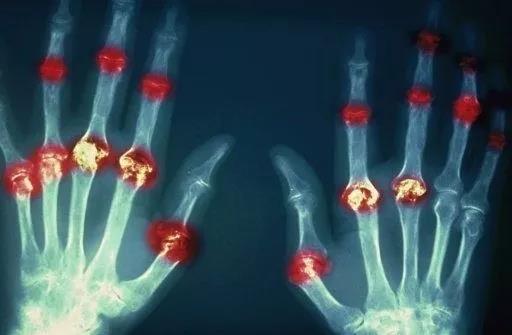

? 類風(fēng)濕關(guān)節(jié)炎

類風(fēng)濕關(guān)節(jié)炎是一種高度致殘的自身免疫性疾病,發(fā)病十年的患者中至少有50%的人失去勞動(dòng)能力。

1977年,Baldwin在用骨髓干細(xì)胞移植治療再生障礙性貧血的過程中,意外發(fā)現(xiàn)患者的類風(fēng)濕關(guān)節(jié)炎得到緩解。

2004年,歐洲骨髓移植和抗風(fēng)濕病聯(lián)盟對(duì)60例類風(fēng)濕病關(guān)節(jié)炎移植患者進(jìn)行回顧性分析,這些患者的關(guān)節(jié)破壞都達(dá)到不可修復(fù)程度,生活不能自理,通過干細(xì)胞移植治療后,67%的患者得到明顯緩解。

我國(guó)國(guó)內(nèi)多家醫(yī)院已開展了干細(xì)胞治療類風(fēng)濕性關(guān)節(jié)炎的臨床研究。首例自體干細(xì)胞移植治療類風(fēng)濕關(guān)節(jié)炎在北京協(xié)和醫(yī)院完成。經(jīng)過5個(gè)月隨訪,這些經(jīng)常規(guī)藥物治療失敗且病情發(fā)展迅速的患者,在接受干細(xì)胞移植治療后,癥狀均獲得改善,關(guān)節(jié)腫脹消失,各項(xiàng)檢查指標(biāo)恢復(fù)正常。

解放軍323醫(yī)院2011年的一項(xiàng)臨床研究中,27位患者(對(duì)照組)只使用藥物治療;另外153位患者(細(xì)胞治療組)在藥物治療的基礎(chǔ)上進(jìn)行臍帶間充質(zhì)干細(xì)胞輸注。結(jié)果顯示,治療組DAS28、HAQ 評(píng)分、ACR20較對(duì)照組下降明顯(分值越低,療效越好),Th1/Th2趨于平衡、Treg升高與臨床實(shí)驗(yàn)指標(biāo)及癥狀的緩解直接相關(guān)。